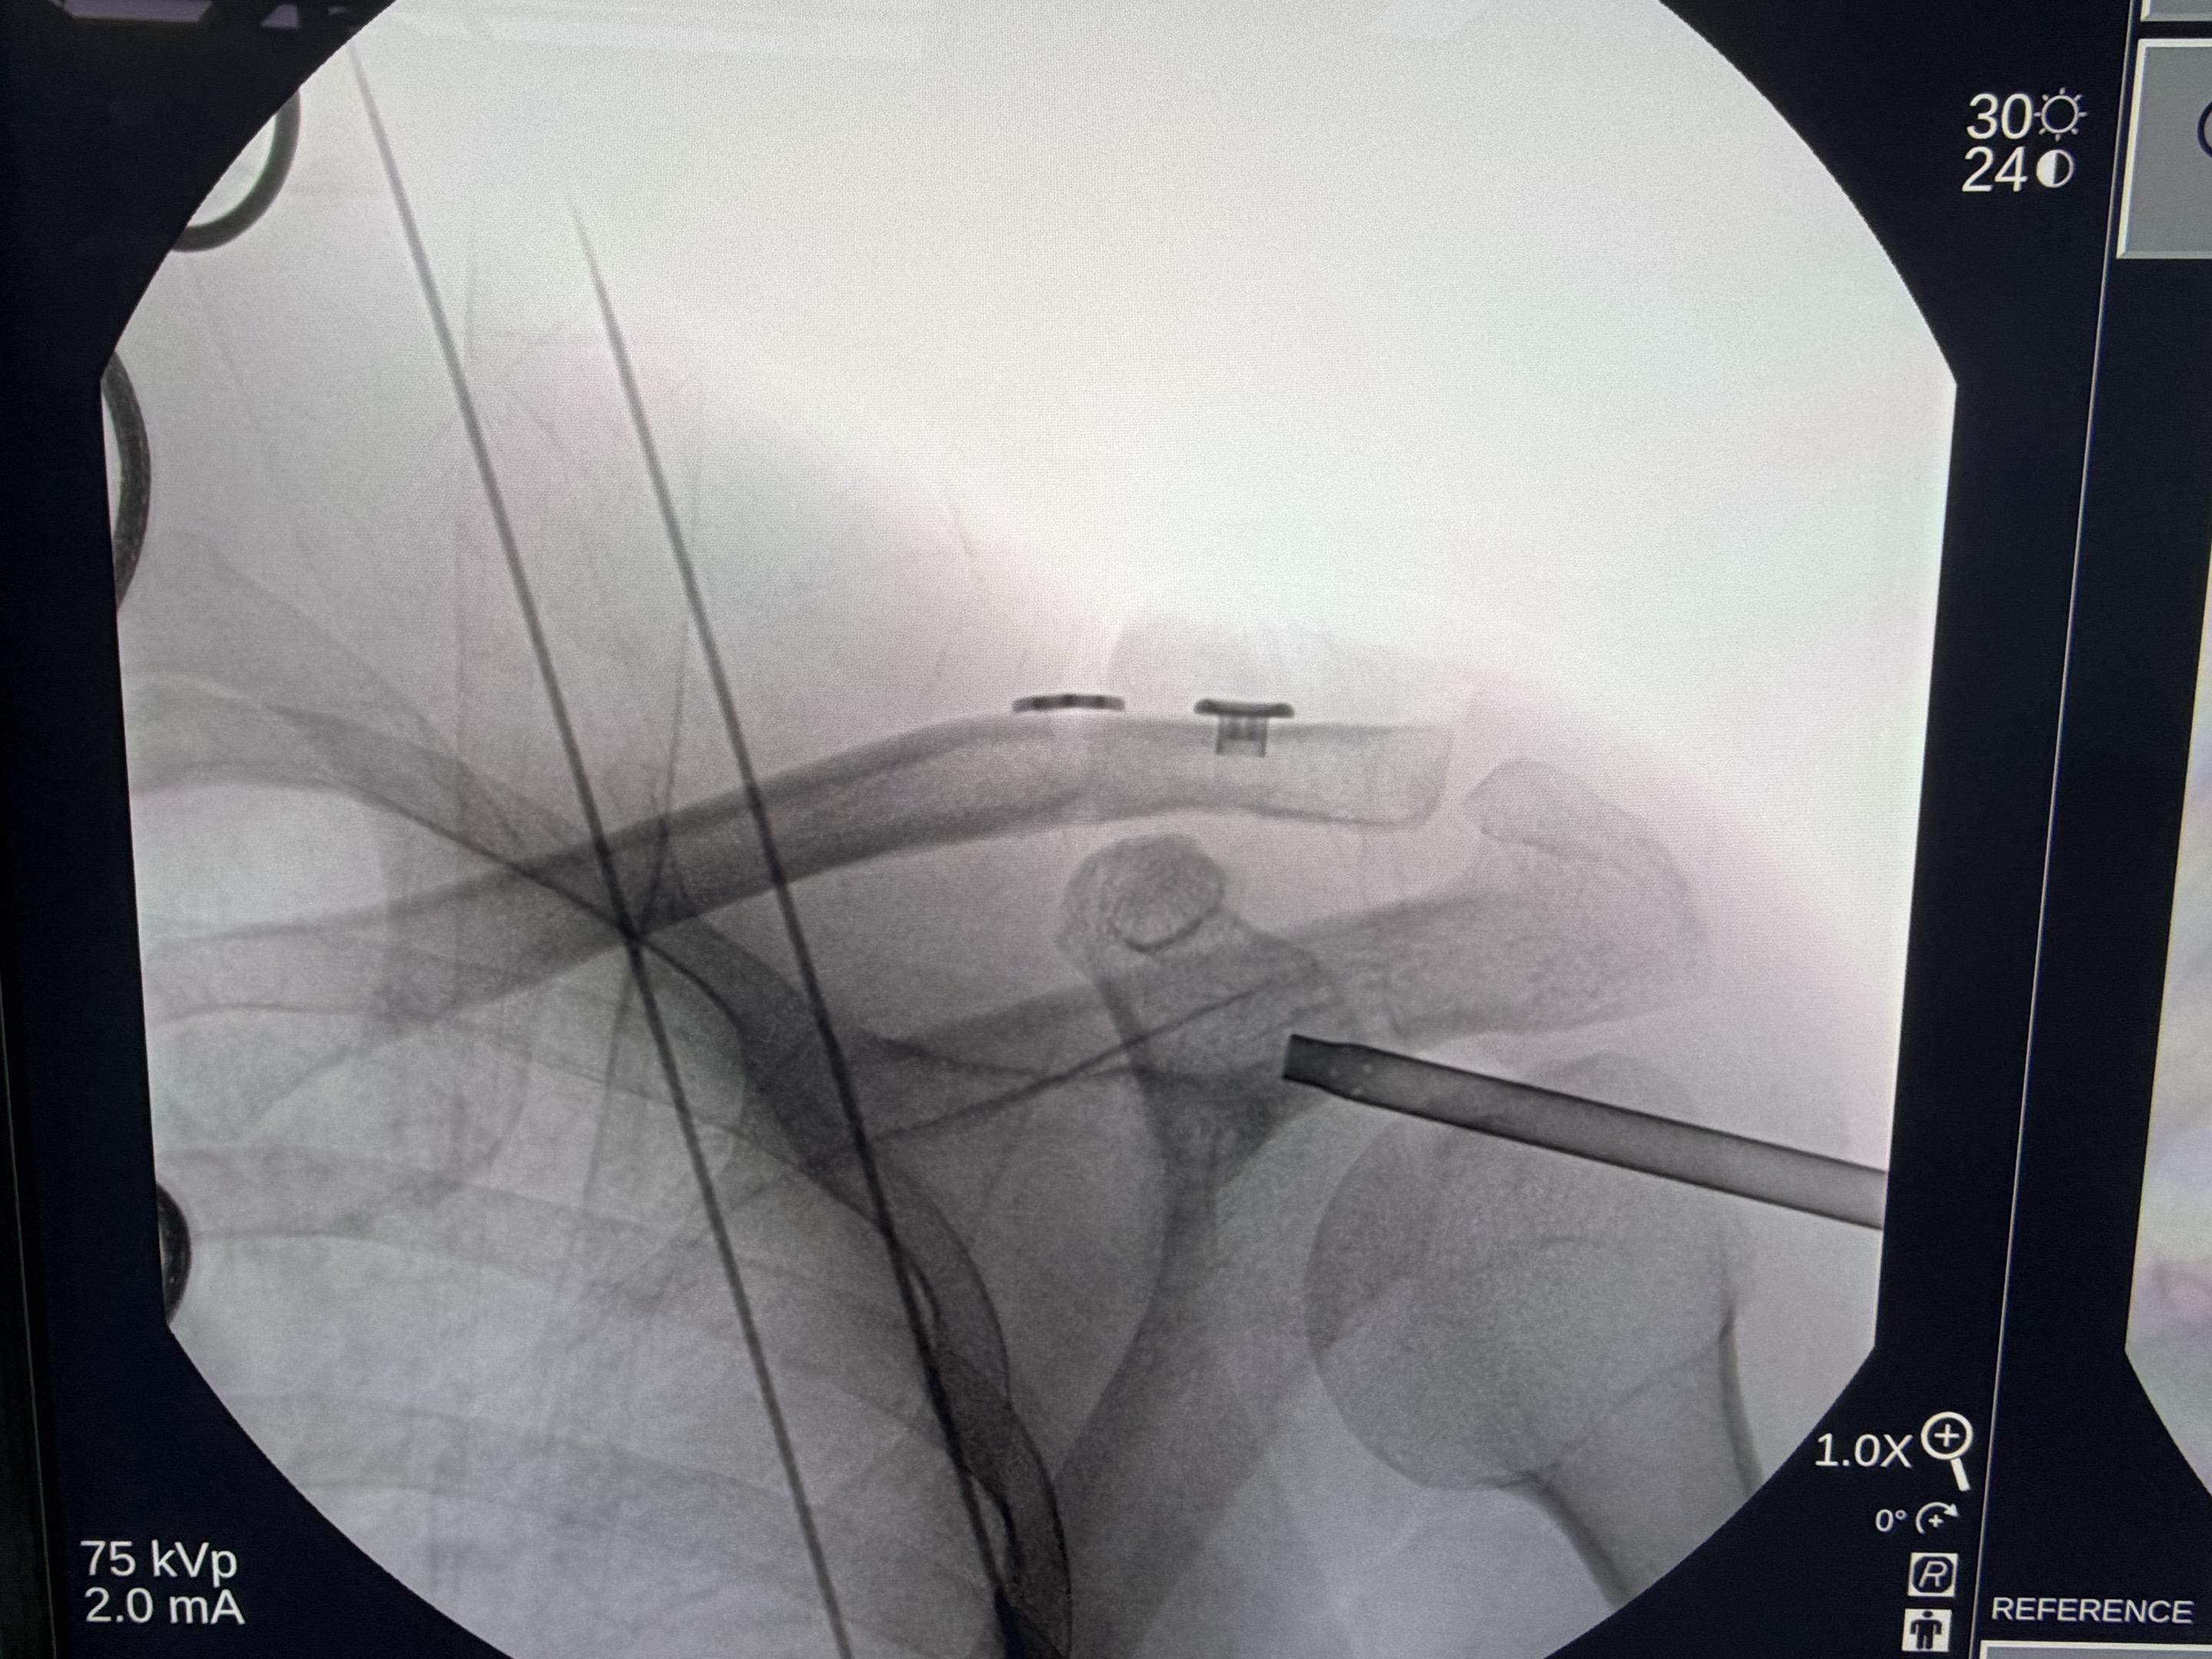

肩锁关节脱位。手术台上的每一次突破,都离不开前辈的倾囊相授。感谢赵立连主任的悉心指导,从理论到细节。